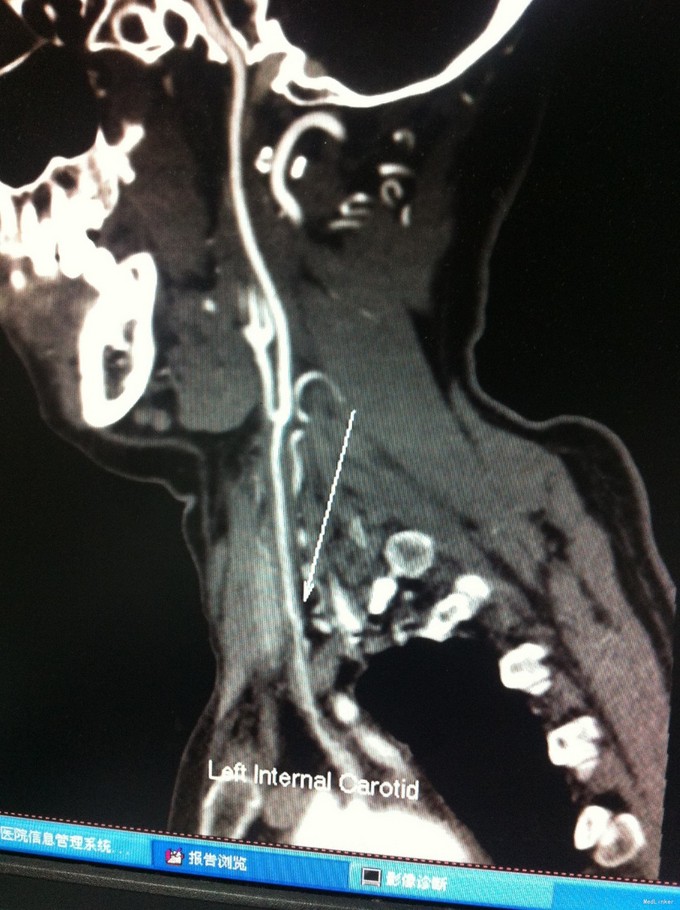

颈总动脉全程狭窄病例一例

动脉狭窄 颈总动脉狭窄

1、眩晕综合征 2、左侧颈总动脉狭窄

随访:该患者拟每三月复查头颈部动脉CTA,定期复查血脂、血糖、血压等情况。目前使用双抗加立普妥治疗。 讨论:患者颈总动脉狭窄、可否行支架植入治疗,个人觉得不可取,请各位专家多提宝贵意见,谢谢。